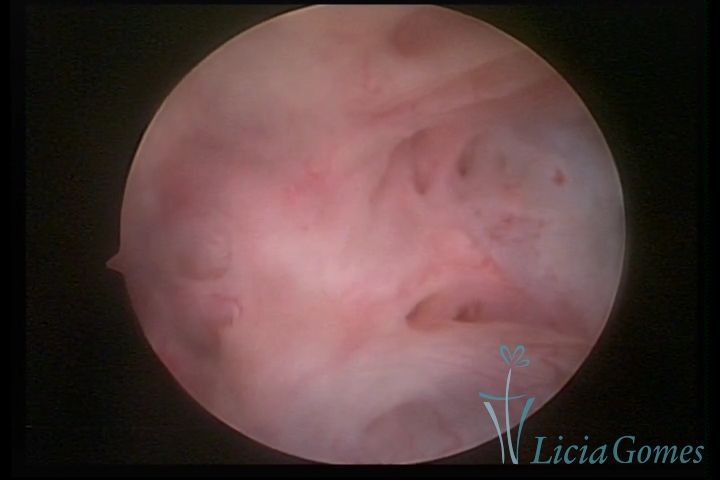

Second part or middle section

In the middle section of the cervical canal, the details of the buds are lost. It is possible to view creases and crypts. Longitudinal grooves are frequently observed. They are the most compact tissues presenting the most vascularized surface, whose vessels follow its passageway.